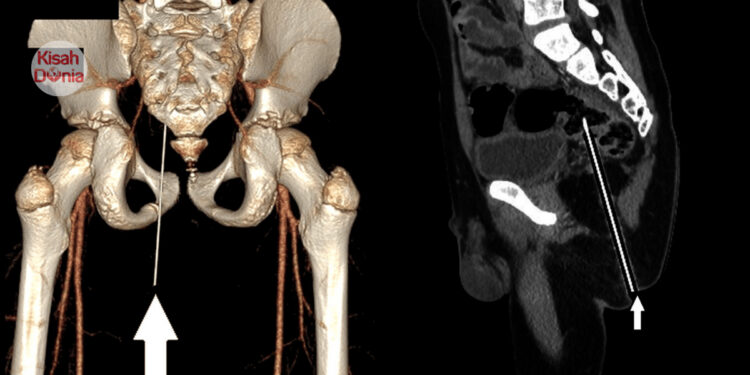

Pensel termasuk ke dalam gluteal sejauh 12.4cm

Walaupun nampak seperti tidak kritikal secara luaran, sebenarnya objek berkenaan telah menembusi daging punggung (gluteal) murid berkenaan sedalam 12.4cm. Imbasan seterusnya turut mengesahkan hujung pensel terbabit sudah terkena pada bahagian rektum (bahagian akhir usus besar).